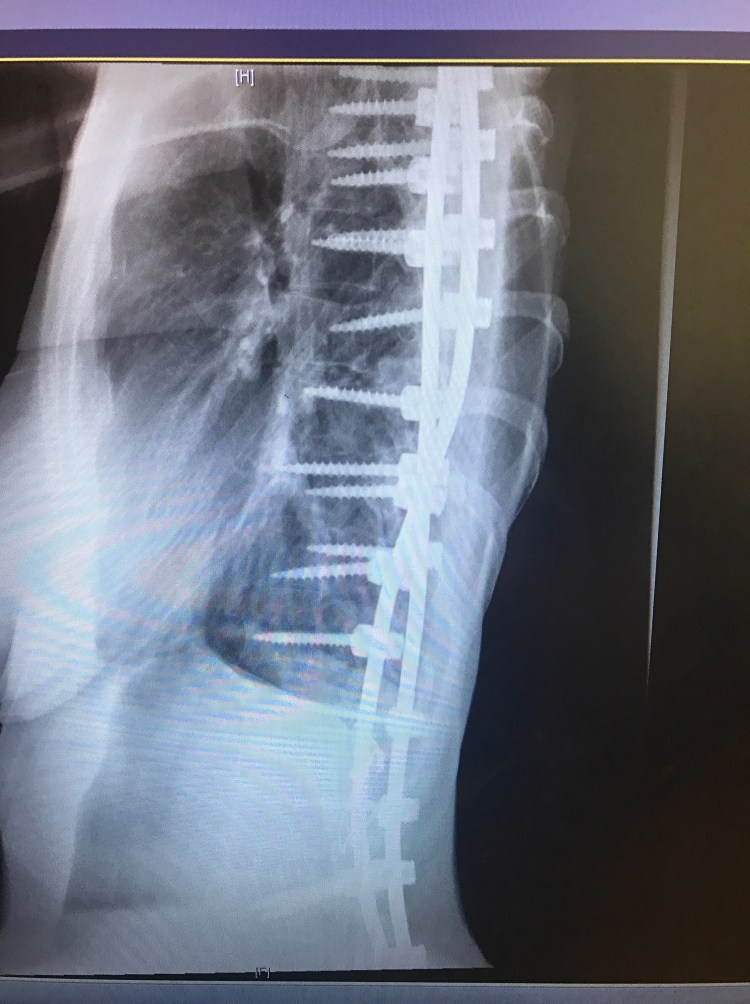

Last week, on Will’s birthday, it was also my 5 month post op appointment. I had a long list of questions and concerns and I was extremely anxious. These appointments always make me nervous and give me anxiety. While in the car on the long drive there, I can’t help but think about everything that happened and how it is going to affect me for the rest of my life. The feeling of these long rods screwed into my spine will never go away although hopefully get easier to forget about over time. I will never be able to bend my back or twist or bend side to side EVER. I still get asked this on a daily basis. The answer is never. Then, I have to continue to be cautious and not slip or fall or do anything that could cause a screw or rod to break and hope upon hope that these rods and screws can last the duration of my life without needing to be replaced. I already know somewhere in the future I will need another surgery to fuse the last few levels to my pelvis and boy am I already dreading for that day to come. Sorry to be a Debbie Downer. I guess it’s hard when people think because I am back at work, or can drive Will to preschool or wrap some damn Christmas presents that I must be “better”. Anyways…..my Doctor said that my bones are fusing. One side is fusing better than the other, but she is hopeful that the other side will catch up. She thinks that the first few months and all the added stress on my body prohibited me from really recovering until just recently. Fusions also can take up to 2 years from surgery to heal completely. All my screws are in place as well. We agreed I need to continue with physical therapy. Last week, I began light core muscle exercises with some resistance to help build my stomach muscles back up. Right now, I am having trouble standing up all the way do to the tightness in my hips and hamstrings. When I am not standing straight, it causes my back muscles to fire up causing some pretty crappy back pain. There’s still a long way to go to get this leg working and my shoulder is still causing me trouble as well. I am also still having blackout and dizzy spells which we had attributed to medicine, however, since being off everything for the most part, I am still having these multiple times a day. I was told I need to see a neurologist and get a primary doctor to run some tests.

You look great. Your xrays look even straighter now!!! Do you live in Cali? Im trying to figure that one out because your dressed like its cold and i thought you lived in Cali. Who was your surgeon again.? God Bless. Your a strong woman and sounds like you have a great supportive husband.

Yes in Northern California. Our weather can be in the 100’s in summer and in the 30’s in Winter. My back is actually a little less straight than right after with settling, but definitely staying put and starting to fuse!